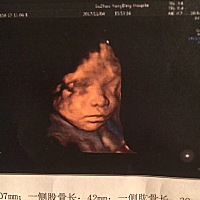

能看出来男孩女孩吗?